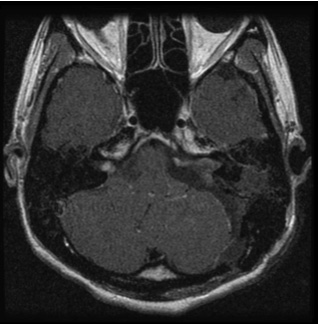

図1:20代男性 聴神経腫瘍

(左図)術前MRI:術前聴力は10dB

(右図)術後MRI:内耳道に筋肉片がおかれている術後聴力は温存16dB 顔面麻痺はなし

図1は若い男性で大きめの腫瘍であったため手術にて摘出しました。術前聴力は良好で、術後もほぼ聴力は変化なく、また顔面神経麻痺も出現していません。